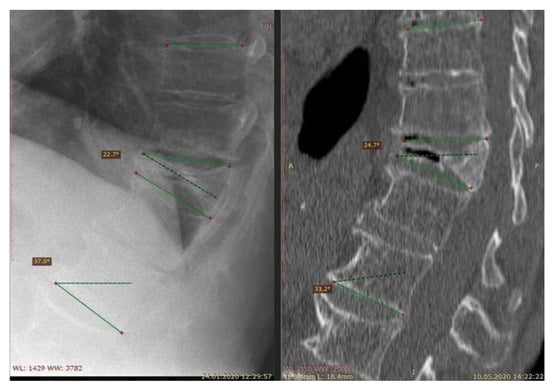

- population: patients suffering from osteoporosis—vertebral fractures diagnosed with an imaging study

7. Diagnostic Methods